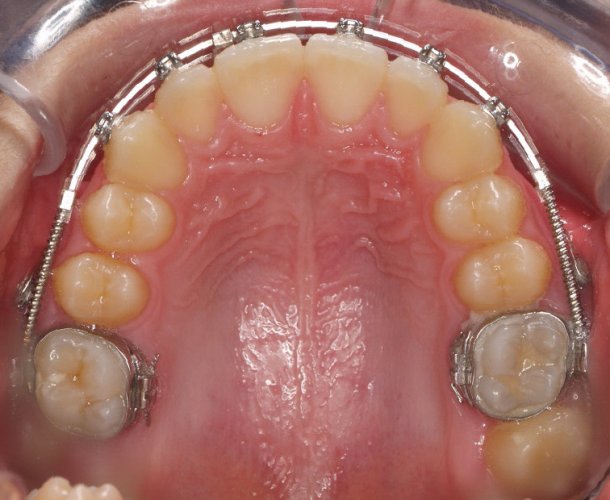

Paciente de 14 años, acude a nuestra consulta por dientes superiores proclinados hacia delante y apiñamiento. El paciente presenta una full clase 2, sobremordida y dientes inferiores proclinados. Decidimos colocarle brackets Damon y microtornillos en maxilar superior para distalizar las muelas. La duración del tratamiento fue de  24meses, y ahora lleva 1 año de contención. El paciente se pone la férula Essix superior 1noche/2 y la de abajo 1noche/semana para mantener.

NOVIEMBRE 2012-Upper Occlusal

Image 4 De 4